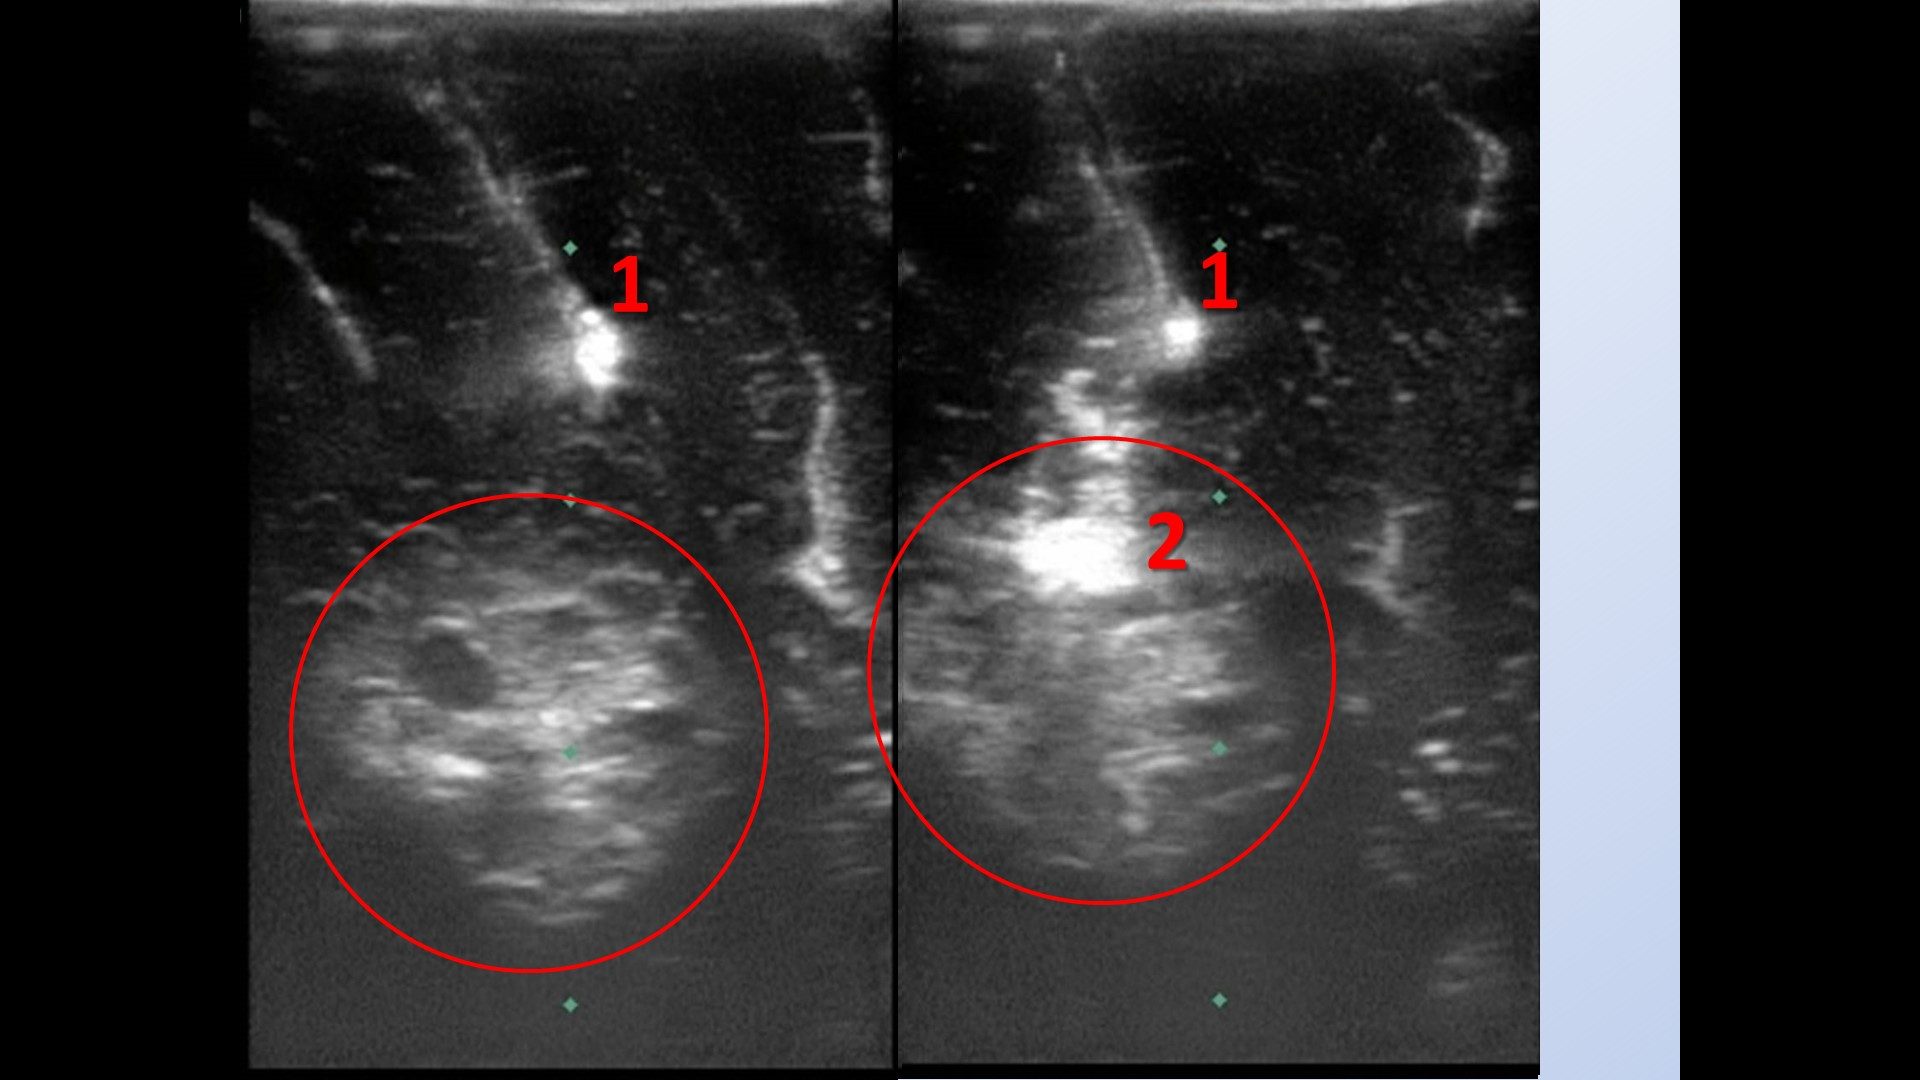

С применением многоэтапной интраоперационной ультразвуковой навигации с применением авторского способа маркировки глубинных структур препарирована борозда между смежными извилинами. На глубине 1 см от дна борозды выявлена кавернозная мальформация с участками кровоизлияния по периферии.

Интраоперационная ультразвуковая навигация с применением эхогенных маркеров: ○ – кавернозная мальформация; 1, 2 последовательно установленные эхогенные маркеры по траектории доступа в щели между смежными извилинами.